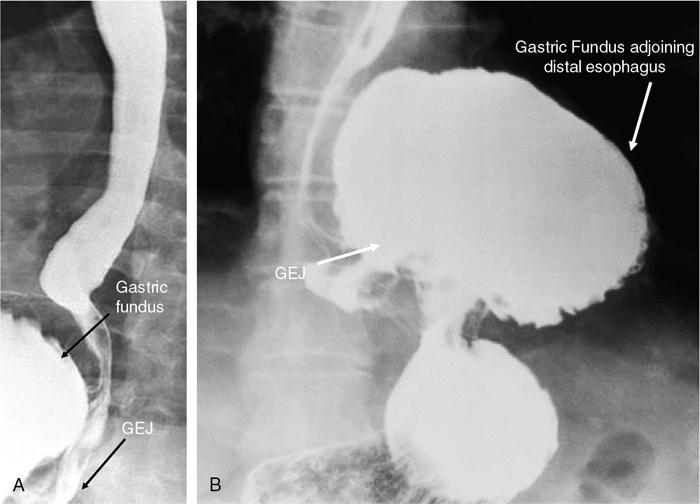

Swarup Nellore, Soumil Vyas, Ujwal Bhure, Ankit Jain, Richa Kothari, Daksh Mehta, Divya Kantesaria, Disha Lokhandwala, Karthik Ganesan The stomach is the most dilated portion of the gastrointestinal tract positioned between the oesophagus and the small intestine occupying the epigastrium, left hypochondrium and umbilical regions of the abdomen performing a multitude of functions including storage and mixing of food and controlling the passage of food into the intestine. Anatomically, the stomach is divided into the following parts (Fig. 8.2.1): the gastric cardia is the portion immediately adjoining the oesophageal opening into the stomach. The fundus is the dome-shaped part above the horizontal plane of the cardiac orifice which undergoes receptive relaxation and is the site of the autonomic pacemaker. The body is the largest part of the stomach extending from the cardiac orifice to the level of incisura angularis (notch like bend in the mid lesser curvature) containing majority of parietal cells (which secrete hydrochloric acid), chief cells (pepsinogen) and enterochromaffin-like cells (ECL). The pylorus is the tubular distal portion of the stomach which is further divided into the gastric antrum and pyloric canal. The pyloric antrum containing G-cells producing gastrin extends from the incisura angularis up to the pyloric sphincter which is an anatomical sphincter formed by concentric thickening of the circular muscle coat and encircles the narrow-slit like pyloric canal. The left dome of diaphragm and oesophagus lie superior to the stomach while the greater omentum and pancreas lie inferiorly. Spleen and liver lie on either side laterally while the transverse mesocolon is located inferolaterally. Diaphragm, greater omentum, left lobe of liver and anterior abdominal wall are anteriorly related to the stomach and contents of lesser sac including pancreas, spleen, splenic artery, transverse mesocolon, left kidney and adrenal gland lie posteriorly. The stomach is embryologically derived from the primitive foregut and is suspended anteriorly by the ventral mesogastrium and posteriorly by the dorsal mesogastrium. During development as the stomach rotates, the peritoneum grows and condenses to form perigastric ligaments, which contain blood vessels, lymphatics, lymph nodes, nerves and fat. The liver forms in the ventral mesogastrium, which develops into the falciform ligament, gastrohepatic ligament (GHL) and hepatoduodenal ligament (HDL). The spleen and pancreas form within the dorsal mesogastrium, which fuses with the posterior abdominal wall to form the gastrocolic ligament (GCL), gastrosplenic ligament (GSL) and splenorenal ligament (SRL). The perigastric ligaments are identified anatomically by the vessels contained in them (Fig. 8.2.2). The gastric cardia and lesser curvature of the stomach are attached to the inferior surface of liver by the lesser omentum by the gastrohepatic ligament respectively which contains the left and right gastric vessels. The inferior free edge of the gastrohepatic ligament extends inferiorly as the hepatoduodenal ligament between the porta hepatis and proximal duodenum gastrophrenic ligament extends between the stomach and the left hemidiaphragm. The gastrocolic ligament identified by the left and right gastroepiploic vessels, connects the greater curvature of the stomach to the anterior surface of the transverse colon. This ligament extends inferiorly as the greater omentum which is a double-layered peritoneum forming a drape anterior to the bowel loops. The gastrosplenic/lienogastric ligament bridges the posterolateral wall of the fundus and greater curvature along the proximal body of the stomach to the splenic hilum and contains the short gastric vessels. The gastrosplenic ligament is contiguous with the lienorenal ligament and both these structures constitute the lateral boundary of the lesser sac. Macroscopically the stomach shows a thick vascular mucosal lining in the form of longitudinal folds called gastric rugae. Microscopic layers of the stomach include mucosa, submucosa, muscularis externa and serosa. The mucosa includes surface mucus cells with simple columnar epithelium, gastric pits, gastric glands, lamina propria and muscularis mucosa. Submucosa includes connective tissue with submucosal Meissner’s plexus. Muscularis externa comprises three smooth muscle layers (longitudinal, circular and oblique) and Auerbach myenteric plexus. The outermost layer called serosa consists of loose connective tissue and visceral peritoneal lining. The arterial supply of stomach is constituted by the branches of celiac artery predominantly in the form of two anastomotic arcades along the lesser and greater curvature. Left gastric artery, a direct branch of the celiac trunk supplies the upper part of the lesser curvature while the lower part is supplied by the right gastric branch of the common hepatic artery arising at the upper border of pylorus. The left gastroepiploic artery, a branch of splenic artery, supplies the upper part of greater curvature and the inferior portion is supplied by the right gastroepiploic artery which is a branch of the gastroduodenal artery. The fundus additionally receives few small short gastric branches from the splenic artery. The veins follow the arteries in their nomenclature. Left and right gastric vein show direct drainage into the portal vein. The splenic vein derives flow from the short gastric and left gastroepiploic vein whereas the right gastroepiploic vein drains into the superior mesenteric vein. Pylorus can be surgically delineated by the prepyloric vein of Mayo lying on its anterior surface. Intrinsic nerve supply consists of the myenteric plexus of Auerbach and submucosal plexus of Meissner. Extrinsic nerve supply consists of sympathetic and parasympathetic components. Sympathetic nerve supply arises from T5 to T9 spinal cord segments supplying the celiac plexus via the greater splanchnic nerve. The plexuses then travel along the respective branches of celiac artery supplying the stomach. Parasympathetic nerve supply is derived from oesophageal plexus of vagus dividing into two vagal trunks. Right (posterior) vagus gives off the posterior gastric branch also called the criminal nerve of Grassi supplying the cardia and fundus of stomach. Right vagus then gives off a celiac branch and continues along lesser curvature of stomach as the posterior gastric nerve of Latarjet supplying the antrum, body and pylorus. Left (anterior) vagus gives off a hepatic branch then continues along the lesser curvature as the anterior nerve of Latarjet supplying the antrum, body and pylorus. Crow’s feet innervation to antropyloric area are important surgical landmarks preserved during highly selective vagotomy receiving branches from both major nerve trunks (anterior and posterior) at the incisura angularis. Anatomical lymphatic drainage is divided into three areas. Area I is the superior two-thirds of stomach draining via the nodes along left and right gastric vessels into the aortic nodes. Area II includes the right two-thirds of the inferior one-third which drains through the nodes along right gastroepiploic vessels via the subpyloric nodes into aortic nodes. Area III includes left one-third of greater curvature draining via short gastric and splenic nodes into suprapancreatic nodes and ultimately into aortic nodes. Gastric lymph node stations are divided into 4 levels with 16 lymph node stations: Paraesophageal nodes below the diaphragmatic hiatus (17) and above the diaphragmatic hiatus (18) are also included. The stomach first appears as a fusiform dilatation in the distal endodermal foregut in the 4th week of embryonic life. The dorsal and ventral mesogastrium suspend the developing stomach to the respective abdominal walls. Preferential growth along the dorsal border of the developing stomach leads to the formation of a convex dorsal border (greater curvature) and a concave ventral border (lesser curvature). The stomach subsequently undergoes a sequence of rotations. The first (90 degrees) clockwise rotation occurs around the longitudinal axis which brings the lesser curvature to the right and greater to the left. This rotation also brings the dorsal mesogastrium towards the left and ventral to the right creating a space behind the stomach called as the lesser sac or omental bursa. The second clockwise rotation occurs around the anteroposterior axis, with the caudal or pyloric part moving upwards and to the right while the cephalic or cardiac portion moves towards the left and slightly downward causing the stomach to assume its final anatomic position. This rotation causes the dorsal mesogastrium to bulge downwards and grow further to eventually become a double-layer apron called the greater omentum. The developing liver divides the ventral mesogastrium into the falciform ligament extending from the ventral abdominal wall to the liver with its lower free edge forming the ligamentum teres, the visceral peritoneum surrounding the liver and the lesser omentum with its two parts – the hepatogastric ligament and hepatoduodenal ligament. The dorsal mesogastrium gives rise to the redundant greater omentum, gastrocolic ligament, gastrosplenic ligament and lienorenal ligament. These perigastric ligaments help us in deciphering patterns of the spread of gastric malignancies and in taking decisions regarding their management and prognostication. These will be further explained in detail under the section of gastric malignancies. An abdominal radiograph is often the initial imaging test for evaluation of acute abdominal pain. The gastric bubble is seen below the left hemidiaphragm in situs solitus. Presence of gastric outlet obstruction may show a distended stomach with gasless small bowel. Hollow visceral perforation is diagnosed by free air seen under domes of diaphragm. Also, the presence and position of various tubes like the nasogastric tube can be confirmed using a radiograph. A fluoroscopic upper gastrointestinal (GI) examination is the radiological study of oesophagus, gastro-oesophageal junction, stomach, duodenum up to duodenojejunal junction by oral administration of contrast. Barium sulphate is a good contrast medium for GI studies as it is radio-opaque, non-absorbable, inert to tissues and can be used for double-contrast studies. Patient should be nil by mouth at least 4 hours prior to the examination. In a single contrast examination, the emphasis is on mucosal relief, luminal distention with contrast material and compression. In the erect position, a small amount of contrast is given to swallow while the oesophagus is visualized under fluoroscopy. The table is then made horizontal and the patient is rotated in a clockwise manner as seen from the foot end of the patient, thus ensuring good coating of the stomach mucosa. Mucosal relief images are then obtained in supine and prone positions to demonstrate the mucosal fold pattern and possible filling defects. After giving some more contrast, the patient is turned oblique with the right side dependent and spot images of the duodenal cap and C loop are taken both in distended and empty states. The patient is again positioned erect and more images of duodenal cap and loop are taken. Further contrast is given to optimally distend the lumen and assess for possible contour abnormalities, wall rigidity and strictures. Compression techniques help assess for filling defects and lesions, in the compressible areas of the stomach. Images are taken in multiple positions – supine, prone, right anterior oblique, right lateral, left posterior oblique in recumbent and right anterior oblique in erect position. Gastric peristalsis and emptying can be observed at fluoroscopy. Advantages of the single contrast technique are that it can be performed quickly, well-tolerated and requires less patient cooperation as compared to double-contrast studies. It can even be performed in physically debilitated patients. Barium is contraindicated in suspected cases of perforation, aspiration, fistula or recent GI biopsy. Single contrast examination can be performed using water-soluble iodinated contrast media in these cases and immediate postoperative patients. Earlier, ionic contrast like Gastrograffin was used. However, due to its high osmolarity, nowadays, non-ionic contrast is preferred as it causes less electrolyte imbalance due to its low osmolarity. Also, it delineates the GI tract very well due to less dilution. Double-contrast studies provide better evaluation of the mucosa than do single-contrast studies. Here, the emphasis is on coating the mucosa with barium and distending the lumen with gas. A well-performed double-contrast study is biphasic and also incorporates some single-contrast techniques. The initial part of the examination is the same as a single contrast examination to obtain the mucosal relief images. Then, gas-forming powder that produces carbon dioxide within the stomach lumen is given with more barium. With the double-contrast technique, the mucosa is coated with a high-density barium suspension and the lumen distended with gas. The patient is rotated in a clockwise manner as seen from the foot end of the patient, thus ensuring good coating of the stomach mucosa. Spot images of the distended stomach are taken followed by the duodenal cap and loop in oblique right-side dependent position. Patient is brought back to erect position erect and more images of stomach, duodenal cap and loop are taken. Further contrast is given to distend the lumen. Residual fluid or food debris in the stomach impairs stomach coating, and lack of adequate coating may preclude visualization of lesions. In addition, optimal gaseous distention is important as underdistention will cause a false appearance of abnormally thickened, and overdistention can obliterate abnormal folds. With normal gastric anatomy, the gastric fundus is best visualized in the upright left-posterior-oblique position, the body in the supine anteroposterior position and the antral-pyloric region in the supine left-posterior-oblique position. The normal gastric mucosal surface should be smooth on double-contrast studies. Areae gastricae appear as reticular networks of polygonal tufts which, owing to the presence of barium in the narrow intervening grooves, are coated with white lines. These are seen most often in the antrum or body of the stomach but can also be seen in the fundus. Areae gastricae are identified on double-contrast studies in 70% of patients and are seen more often in elderly patients. Polygonal tufts should normally range in size from 2 to 3 mm in the antrum and 3 to 5 mm in the body and fundus. Normal gastric folds are more prominent in the proximal to mid stomach and more undulating along the greater curvature as compared with the lesser curvature. Antral folds should be typically effaced with the double-contrast technique. Gastric cardia is characterized by three or four stellate folds radiating from a central point at the gastro-oesophageal junction; this is known as the cardiac rosette and is best visualized in the supine right-lateral position. Ultrasonography (USG) is the modality of choice to visualize hypertrophic pyloric stenosis in infants. Although USG does not play much of a role in adults for imaging of stomach due to reflection of sound waves by air, luminal distension with water may enable to identify mucosal – submucosal pathologies and to assess perigastric relationships in pathologies. CT can not only evaluate the location and anatomy of the stomach, but also provide additional information about the relationship of the stomach to surrounding structures. An optimal CT examination of the stomach includes good stomach distension with a well-visualized wall. Gastric distention can be achieved by the oral administration of negative or positive luminal contrast. Positive contrast agents include a 1%–2% barium suspension or a 2%–3% solution of a water-soluble iodinated contrast agent. Water-soluble agents should be used in cases of suspected perforation. Positive agents provide a bright lumen with better identification of luminal encroachment or diverticula but may limit detailed evaluation of gastric wall enhancement. Positive contrast also may not mix well with gastric contents, producing a pseudotumor appearance. On the other hand, neutral or negative contrasts agents, usually water, produce a low attenuation lumen which allows for more detailed evaluation of the gastric wall and its enhancement pattern following intravenous contrast and is preferred for three-dimensional imaging. Multidetector CT with thin collimation allows for postprocessing in any orthogonal plane. The CT data of the stomach can be manipulated to simulate endoscopic images (virtual gastroscopy). This display technique accentuates the stomach wall and folds. Prior to evaluating the stomach with CT, oral contrast is administered at repeated intervals as well as immediately prior to scanning. Multiphasic scanning after intravenous contrast may be employed at 25–35 seconds (late arterial), 55–75 seconds (venous phase) after contrast injection. Normally, the gastric wall may enhance to approximately 120 Hounsfield Units after intravenous contrast administration. The mucosa may enhance more than the relatively lower-attenuation muscularis propria. Abnormal enhancement of the wall can highlight pathologic processes. The CT appearance of the stomach also depends upon the degree of distention. When well distended, the body and fundus is less than 5 mm thick, though the normal antrum may appear slightly thicker. The presence and pattern of wall enhancement, degree and location of wall thickening, and length of an involved segment may be assessed. Comprehensive MRI examination of the stomach and duodenum by the combined use of T2-weighted single-shot and T1-weighted gradient echo (GRE) – with and without fat suppression, and gadolinium-enhanced 3D GRE helps to detect the spectrum of gastric diseases on MRI. These sequences minimize artefacts from bowel peristalsis, increase the sensitivity of detection of peritoneal and serosal disease by suppressing the high signal of intra-abdominal fat, widen the dynamic range of abdominal tissue signal intensities and distinguish between intraluminal bowel contents and bowel wall. The gastric rugae are well seen on T2-weighted single-shot spin-echo images and their enhancement appears as bands of enhancing tissue arranged perpendicular to the external contour of the gastric wall. The normal gastric wall enhances more intensely than other segments of bowel on immediate postgadolinium SGE images. Water is frequently used as an oral contrast agent when imaging the upper GI segment-stomach and duodenum. Noninvasive dynamic study for assessment of gastric motor function and wall motility can also be done using MRI for diagnosis of gastroparesis. Gastric emptying scintigraphy (GES) is a well-established radionuclide procedure to evaluate patients with suspected gastric motility disorder, more so for non-invasive assessment of gastroparesis in patients with symptoms of postprandial fullness, nausea, vomiting, abdominal pain, bloating, early satiety, loss of appetite, as well as weight loss. Gastroparesis, commonly seen in diabetics, is a condition that affects the normal spontaneous movement of the gastric muscles, leading to impairment of gastric motility, because of which the stomach cannot empty itself of food in a normal fashion and time. GES can also provide useful information with regards to assessment of impaired gastric motility in patients with GERD (gastro-oesophageal reflux disease) unresponsive to routine therapy, diabetics with poor glycemic control, and also in patients with colonic inertia who are being considered for colectomy (since benefits of colectomy are mitigated in patients with concurrent impaired gastric emptying). On the other hand, GES is also useful for assessment of rapid gastric emptying (GE), which is a major factor in dumping syndrome, often seen post peptic ulcer surgery, with or without vagotomy. The solid or liquid component of a meal is radiolabelled with a radiopharmaceutical, which is consumed by the patient and subsequently measured gastric radioactive counts by scintigraphy correlate with the volume of the meal remaining in the stomach. Solid-phase GES is used for the evaluation of gastric motility disorder/gastroparesis. Liquid-phase gastric emptying is generally not clinically useful since it is often in the normal range in spite of deranged emptying for solids even with severe gastroparesis. The preferred radionuclide meal for the gastric emptying scintigraphy includes egg-white radiolabelled with 0.5–1.0 mCi of Technetium-99m (99mTc) [approximate caloric value of 255 kcal]. Two large eggs (egg-whites), two slices of bread, fruit jam, water (120 mL approximately), and the radiopharmaceutical (0.5–1.0 mCi of 99mTc–sulphur colloid). For patients allergic, to eggs, alternative meals like oatmeal or Liquid Ensure nutrient supplement can be used. Reporting should include the percentage of radiotracer retained in the stomach at defined time intervals. The normal reference values for comparison are as follows: Grading the severity of the delay in gastric emptying based on gastric retention at 4 hours of the study: Gastro-oesophageal reflux (GER) is a common condition in infants and children, wherein there is reflux of stomach contents into the oesophagus, due to possible incompetence of gastro-oesophageal sphincter, which can lead to development of symptoms like regurgitation, heartburn, cough and dyspepsia. Children can present with recurrent respiratory infections, iron deficiency anaemia and failure to thrive. It is often a self-limited process in infants and children which usually resolves by 12–18 months of age. On the other hand, gastro-oesophageal reflux disease (GERD) is a chronic pathological process which can be troublesome. Scintigraphic evaluation of gastro-oesophageal reflux, popularly known as ‘milk scan’, is an established imaging modality and has sensitivity of 75%–100%. This radionuclide test for gastro-oesophageal reflux is physiological and quantitative and commonly used for diagnosis in neonates and infants. Four hours fasting is preferred. A liquid meal consisting of formula, milk, or orange juice mixed with the radiopharmaceutical is administered either orally or by nasogastric tube. 99mTc–sulphur colloid. Dose: 0.2 to 1 mCi. After administering the liquid meal and allowing burping, the baby is positioned supine under the gamma camera detector head, including chest and upper abdomen in the field of view. A radioactive marker can be placed at the mouth. Anterior serial dynamic planar images are acquired for around 60 minutes with a framing rate of 5–10 seconds per frame. Delayed anterior static image of the chest may be acquired additionally. The acquired frames are reviewed in cinematic display for visual estimation and to look for reflux of the radiotracer into the oesophagus. Reflux is seen as distinct spikes of radiotracer activity into the oesophagus. For quantitative estimation, the volume of each episode of reflux, frequency of episodes and rate of reflux clearance from the oesophagus are taken into consideration. Percentage of reflux is calculated by drawing an ROI over the oesophageal spike of radiotracer activity and the counts are calculated and expressed as a fraction of the gastric activity counts. Values greater than 5% are suggestive of reflux. Semiquantitative evaluation grades each reflux event: Based on this, four categories can be formulated: The greater the number of high-level reflux events and the longer they last, more severe is the gravity of the problem. Pulmonary aspiration should also be looked for, though the sensitivity of detection is poor. Liquid gastric emptying can be evaluated during the same study up to 2 hours. Normal values for liquid gastric emptying are: Endoscopy is the preferred examination to evaluate for majority of the upper GI symptoms. It is very sensitive in detecting mucosal lesions and simultaneously, biopsies can be taken. In cases of upper GI bleed, endoscopy can not only detect the site and cause of the bleed, but also further treatment like adrenaline/sclerosant injection or ligation can be done. EUS can provide detailed assessment of the 5 layers of the gastric wall and is thought to be the most accurate non-surgical method for local tumour staging (Fig. 8.2.9). For subepithelial (submucosal) gastric lesions, EUS can assess the echogenicity of a lesion, the exact layer of the gastric wall which is involved (accurate T-staging of a tumour) and assess for the presence of blood flow with Doppler ultrasound to help ascertain the likely aetiology. EUS-guided fine needle aspiration may also provide additional diagnostic information. Hiatus hernia is a common positional abnormality of stomach, characterized by herniation of abdominal contents, commonly the gastro-oesophageal junction and stomach, into the mediastinum above the diaphragm through a widened oesophageal hiatus. The oesophageal hiatus is an elliptical opening with complex anatomy formed by the right and left crus of the diaphragm. However, the most common anatomical description is of the right crus splitting into two bundles, the right and left, which form a sling encircling the distal oesophagus and may be reinforced by the left diaphragmatic crus. The distal oesophagus is typically anchored to the oesophageal hiatus by a main restraining structure which is the phrenicoesophageal ligament/membrane (the fascia of Laimer) which is a condensation of endo-thoracic and endo-abdominal fascia and this membrane circumferentially inserts into the oesophageal musculature in close proximity to the squamocolumnar junction (SCJ). The ligament maintains the competence of the oesophageal hiatus and prevents rostral herniation of the gastro-oesophageal junction and stomach. During normal physiological swallowing, the longitudinal layer of the oesophageal muscularis propria contracts with associated oesophageal shortening and stretching of the phrenicoesophageal ligament/membrane resulting in the transient elevation of the oesophagogastric junction and portion of the stomach above the hiatus. At the end of the swallowing mechanism, the elastic recoiling of the phrenicoesophageal ligament/membrane restores the migrated segment to its normal position. With ageing-related wear and tear, the ligament becomes lax with progressive depletion of elastin fibres resulting in proximal migration of the gastro-oesophageal junction and stomach. Other potential risk factors of fibromuscular degeneration are caused by increase in the intra-abdominal pressure as occurs in obesity and pregnancy. The majority of the symptomatic cases of hiatal hernia present with the clinical symptoms of gastro-oesophageal reflux disease (GERD) with most characteristic manifestations of acid regurgitation, heartburn, dysphagia, epigastric or chest pain and even chronic iron deficiency anaemia. Large hernias may also present with early satiety. Conventionally, hiatus hernias are classified into sliding and paraesophageal varieties. The current comprehensive anatomic classification has evolved to include a categorization of hiatal hernias into Types I–IV and is necessary especially regarding the treatment approach, as indications for the surgical method are quite different between sliding and paraesophageal hernias. Majority of hiatus hernias (95%) are sliding hiatus hernias (type I), the remaining type II–IV hernias as a group are referred to as paraesophageal hernias (PEH), with more than 90% of these comprising type III, and the least common being of type II. The assessment of hiatus hernia can be done by various modalities including radiological, manometry and endoscopy studies. The diagnosis of a large hiatus hernia is straightforward, however, identifying a small one is challenging due to mobility of the gastro-oesophageal junction during physiological process like deglutition and respiration. According to the SAGES Guidelines, only those investigations which will alter the clinical management of the patient should be performed. Radiological investigations are usually indicated for diagnosis and presurgical evaluation. Plain chest radiographs demonstrate opacity within the chest typically in the midline overlapping the cardiac shadow or paramedian location (Fig. 8.2.14A), with or without an air-fluid level. Barium swallow radiography is still considered an easy tool for diagnosis of hiatus hernia and provides essential information about the size, location, motility dysfunction, stricture secondary to GERD and stenosis. The evaluation of hiatus hernia requires understanding of anatomical radiographic landmarks like phrenic ampulla, A ring and B ring (or Schatzki’s ring) on a barium study (Fig. 8.2.14B). The phrenic ampulla is a globular structure seen above the diaphragm and below the tubular oesophagus during a contrast swallow. The A ring represents a muscular ring visible at the upper margin of the phrenic ampulla and physiologically corresponds to the highest-pressure zone within the lower oesophageal sphincter, this is often seen as a transient indentation on the oesophageal lumen. The B ring identified in about 15% of individuals, representing the mucosal ring corresponds to the squamocolumnar junction (Z line) and divides the phrenic ampulla into the oesophageal vestibule (A ring to B ring) and the sliding hiatus hernia (B ring to the stomach below the diaphragm). The B ring is a persistent constriction which is not usually not more than 2–3 mm and despite mucosal, can sometimes be symptomatic and require dilatation. By convention, there must be a distance of 2 cm or more between the B ring and the hiatus, to call it a hiatus hernia as physiological migration up to 2 cm is known in normal individuals. Although not reliable, barium studies may also provide information about a short oesophagus, which is identified as a tubular straightened oesophagus with the oesophagogastric junction fixed far above the diaphragm and may be stenotic, the intrathoracic herniated stomach revealing a more elongated funnel/bell – shaped configuration. Cine fluoroscopy provides further additional information about the bolus transit through gastro-oesophageal junction. The major drawbacks of the procedure are non-visualization of B-ring in majority of the cases, radiation exposure, barium/iodine hypersensitivity, contraindication in pregnancy and increase risk of aspiration in paraesophageal hernia causing pneumonitis. Computed tomography (CT) scan is not routinely advised for the primary diagnosis of hiatus hernia but is indicated in cases of suspected complications like volvulus in paraesophageal hernia, obstruction, perforation and strangulation. Multi-slice CT with reconstruction in sagittal, coronal planes and 3D reformations have increased the sensitivity of CT in detection of hiatal hernia. Oesophagogastroduodenoscopy gives added advantage of real-time visual assessment of the mucosa of the oesophagus, stomach and duodenum. The common diagnostic criteria in endoscopic is proximal migration of gastro-oesophageal junction by >2 cm. Endoscopy can also determine the presence of erosive esophagitis or Barrett’s oesophagus. Further, the inability or difficulty of negotiating the scope into duodenum in the presence of a large hiatal hernia is diagnostic of paraesophageal hernia with volvulus. Evaluation of gastric viability is also important in patients undergoing emergency surgery for incarcerated hernias. The disadvantage of the procedure is lack of reproducibility; retching or belching of the patients during examination which can alter the location and anatomy of GEJ and excess air insufflation of the stomach which may exaggerate the size of the hernia. Oesophageal manometry is measured at the level of the diaphragmatic crura, however, manometric landmarks differ from that of barium study and endoscopy, and identified by pressure inversion point. In patients with a paraesophageal hiatal hernia, placement of the manometry catheter across the lower oesophageal sphincter and below the diaphragm can be difficult. The procedure is planned before surgery to exclude motility disorders like achalasia and to verify the integrity of oesophageal peristalsis. pH testing is not essential in the diagnosis of a hiatal hernia, but is necessary for a quantitative analysis of reflux in a case of hernia which can be relieved by antireflux surgery. Confirmation of abnormal gastro-oesophageal reflux on upper endoscopy, or increased oesophageal acid exposure on pH monitoring is necessary prior to operative intervention in patients with a sliding hiatal hernia. Nuclear medicine studies, transoesophageal echocardiogram (TEE) and endoscopic ultrasound (EUS) can also demonstrate hiatal hernias but are not routinely used for diagnosis. The main aim of treatment in symptomatic patient is to reduce the acid reflux. Lifestyle modifications are the first line of management and include weight loss, elevating the head of the bed preferably by 8 inches during sleep, avoidance of meals for atleast 2–3 hours before bedtime and elimination of ‘trigger’ foods. According to the SAGES Guidelines updated in April 2013, the treatment protocols are provided on the basis of types of the hiatus hernia. Type I (sliding) hiatus hernia are usually managed with proton pump inhibitors for 8 weeks, once or twice daily depending on the symptoms. Other alternatives are H2 receptor antagonists and antacids. If the patient is not relieved symptomatically by medication, surgical repair like laparoscopic fundoplication (Nissen or Toupet) can be done. Steps of fundoplication comprise surgically relocating the gastro-oesophageal junction below the diaphragm, maintaining an oesophagogastric angle to prevent gastro-oesophageal reflux, constructing a gastric wrap around the distal oesophagus to support the distal oesophageal sphincter and increase its resting pressure, and finally approximate the diaphragmatic hernia to narrow the widened hiatus. In all symptomatic Type II, III and IV hiatus hernia, surgical repair is strongly recommended as the primary treatment, particularly those with acute obstructive symptoms or which have undergone volvulus. Routine elective repair of completely asymptomatic paraesophageal hernias may not always be indicated and determinants for surgery should include the patient’s age and co-morbidities. These fundoplication surgeries are described later in the text. Gastric volvulus is an uncommon entity and characterized by abnormal rotation of the stomach (usually >180°) along the long or short axis, leading to variable degree of gastric obstruction, which can be of a closed-loop type resulting in strangulation. The exact incidence of gastric volvulus is unclear as patients with a chronic presentation may never be diagnosed.2 Approximately, 10%–20% cases of gastric volvulus occur in children less than 1 year, while the other 80% cases are detected in adults, of which 80%–90% are often encountered in the fifth decade of life.3 No significant predilection is seen with either sex or races. Gastric volvulus can be classified on the basis of aetiology, axis of rotation and duration of onset. While classification based on axis of rotation by Singleton is widely accepted and more relevant to the radiologist, classification based on duration of onset of symptoms is more relevant in clinical assessment. On the basis of axis of rotation (Fig. 8.2.15), gastric volvulus is divided into organoaxial volvulus, mesenteroaxial volvulus and the rarest combined/mixed type. Organo-axial volvulus, by far, the most common type of gastric volvulus, encountered often in the elderly, is characterized by rotation of the stomach along its long axis, that is, cardio-pyloric axis, and resulting in an ‘inverted stomach’ with a horizontal orientation, in the form of anterosuperior displacement of the antrum and posteroinferior rotation of the fundus, so that the greater curvature is displaced superiorly and lesser curvature caudally in the abdomen (Fig. 8.2.16). The site of obstruction in this type of volvulus is at the cardia or at pylorus. It has a higher predisposition towards strangulation and ischaemia. Organo-axial volvulus also shows association with the paraoesophageal hernia or diaphragmatic defects, which allows abnormal movement of the stomach along the long axis. If the degree of rotation is less than 180 degrees, the patient may have an incomplete or partial volvulus which is not completely obstructing and may be asymptomatic; it may be more appropriate to describe it as organo-axial position rather than volvulus. Mesenteroaxial volvulus is less commonly encountered (30%) and accounts for about 29% of cases, is reported more often in young adults or children. It occurs when the stomach rotates around its short (transverse) axis, that is, line connecting the midpoint between the lesser curvature and the greater curvature of the stomach, leading to a vertically oriented stomach, with anterior rotation of the pylorus, antrum and resultant displacement of the antrum above the gastro-oesophageal junction (Figs 8.2.17 and 8.2.18). The site of obstruction is usually at antropyloric region. It is usually not associated with a diaphragmatic defect and is often idiopathic. The third and rarest type of gastric volvulus is the combined type when the stomach shows both rotation along the short and long axes. Based on aetiology of rotation, gastric volvulus can be subdivided into either primary or secondary. Primary gastric volvulus representing 25%–30% of the cases, is more common in the adults. It occurs in the subdiaphragmatic location due to abnormality in the gastric fixation, exclusively because of disruption, laxity or absence of the gastric ligaments which anchor the stomach in place. These ligaments namely the gastrohepatic, gastrocolic, gastrophrenic, gastrosplenic and gastropancreatic ligaments, along with gastro-oesophageal junction and pylorus, provide anchorage and fix the stomach in place intra-abdominally, and prevent abnormal rotation of the mesentery. The primary gastric volvulus usually presents with the mesenteroaxial type of anatomical configuration. Around 70% of patients present with secondary gastric volvulus occurring due to abnormal rotation around the lead point formed by associated disease. The most common association of gastric volvulus is seen with paraoesophageal hiatus hernia. Other causative factors of volvulus include congenital or traumatic diaphragmatic hernia, diaphragmatic paralysis, eventration, connective tissue disorders, previous surgery, adhesions, peptic ulcer, neoplasm, splenomegaly or absence of the spleen and colonic overdistension. On basis of clinical presentation and speed of onset, gastric volvulus can be acute, subacute or chronic. Acute gastric volvulus is a surgical emergency and usually presents with sudden onset epigastric pain, distension, non-bilious vomiting or severe retching, depending on the degree of obstruction. The Borchardt triad of acute volvulus comprises severe epigastric pain and distention, retching but inability to vomit, and difficulty or impossibility of passing a nasogastric tube and may be observed in 70% of cases. Other symptoms include hematemesis due to mucosal sloughing in stomach gangrene or mucosal tear due to retching, dysphagia and dyspnea. Even after prompt treatment, mortality of acute gastric volvulus can be up to 30%–50%, likely secondary to gastric ischaemia, perforation or necrosis resulting from severe gastric obstruction (closed-loop obstruction) causing vascular compromise, making it a life-threatening surgical emergency. Chronic gastric volvulus represents spectrum of diseases from long-standing partially obstructed volvulized stomach with incomplete gastric obstruction on the one side, and intermittent volvulus of stomach with recurrent episode of acute symptoms as the other presentation. Chronic gastric volvulus usually presents with intermittent complaints of vague epigastric pain, non-bilious vomiting, dysphagia or early satiety, dyspepsia and sometimes regurgitation. Due to nonspecific clinical symptoms, diagnosing gastric volvulus is very challenging on the first instance and requires a high clinical suspicion. Diagnostic imaging, along with clinical findings are usually required to achieve the correct diagnosis, and also plays major role in excluding the other common differential diagnosis, like pancreatitis, cholecystitis or pneumonitis etc. The diagnostic modalities useful in suspected cases of gastric volvulus are plain radiographs, upper gastrointestinal contrast (barium) studies, computed tomography and upper gastrointestinal endoscopy. Plain chest and abdominal radiographs may reveal a radiolucent hollow viscus, with or without an air-fluid level, in the chest (when associated with PEH) or upper abdomen. The presence of a nasogastric tube may assist in identifying a malpositioned stomach, and administration of contrast via the nasogastric tube may be confirmatory in this regard. Furthermore, chest radiographs may identify evidence of underlying anatomic abnormalities predisposing to gastric volvulus, including elevated hemidiaphragm due to phrenic nerve palsy or diaphragmatic eventration and rib fractures suggesting prior thoracoabdominal blunt trauma. The plain radiographs may show two air-fluid levels in the antrum and fundus, or a single air bubble with no additional luminal gas in the supine position. A retrocardiac air-fluid level may be seen secondary to hernia and presence of intramural air (gastric emphysema) can be visualized as a radiolucent stripe in the gastric wall. At times a large hiatus hernia may be complicated by volvulus (Fig. 8.2.19). Passage of orally administered contrast like barium can demonstrate the anatomy and also assess the degree of obstruction. As mentioned above, the position of the gastric curvatures and the gastro-oesophageal junction are useful in differentiating the anatomical subtype of volvulus. Computed tomography may be more feasible in an acute emergency setting in order to identify abnormal gastric position, axis and multiplanar reconstructions, especially in the coronal plane, can well elucidate the findings and an associated complication like ischaemia. CT has an overall 90% accuracy in the diagnosis with identification of gastro-oesophageal junction and pylorus lying in close proximity to each other and the transition point at the pylorus known to have 100% sensitivity and specificity. Abnormal antral folds may be seen secondary to the twisting. Stenosis at the neck of the hernia is the CT finding with the second-highest sensitivity (77%–80%) and specificity (94%–97%). CT findings of oedematous or hypoenhancing gastric wall, pneumatosis, pleural effusion or pneumoperitoneum, as indicators of gastric ischaemia are not common but specific when identified. An upper gastrointestinal endoscopy confers both diagnostic and therapeutic benefit, although it may establish the diagnosis in only 28%–45% patients and also, the endoscopic procedure may reduce the volvulus missing the diagnosis by an unwary endoscopist. However, it still remains the best method to detect mucosal ischaemia. Flexible endoscopy also has the advantage of placing a nasogastric tube as it may not be possible with a blind technique at the bedside in the setting of organoaxial volvulus and an obstructed gastro-oesophageal junction. Nasogastric decompression forms the initial management of gastric volvulus with emergent laparotomy or laparoscopy to assess gastric viability, resect gangrenous portion if any and perform de-rotation and gastropexy (fixation of the stomach to the diaphragm and/or the anterior abdominal wall) with or without gastrostomy with repair of secondary factors like paraoesophageal hernia. Erosions are focal shallow areas of ulcerations confined to the epithelium or lamina propria without extending through the muscularis mucosae into the submucosa. NSAIDs are the most common cause of gastric erosions while other incriminated factors include Helicobacter pylori infection, alcohol, viral infections, Crohn’s disease, stress and iatrogenic trauma. Erosions may be visible on double-contrast barium examination obtained with good mucosal coating, as multiple tiny 1- to 2-mm collections of barium, often with a surrounding mound of oedema appearing as a filling defect in the barium pool (Fig. 8.2.20). They are usually located in the gastric antrum and tend to occur along thickened folds.

Gastric volvulus